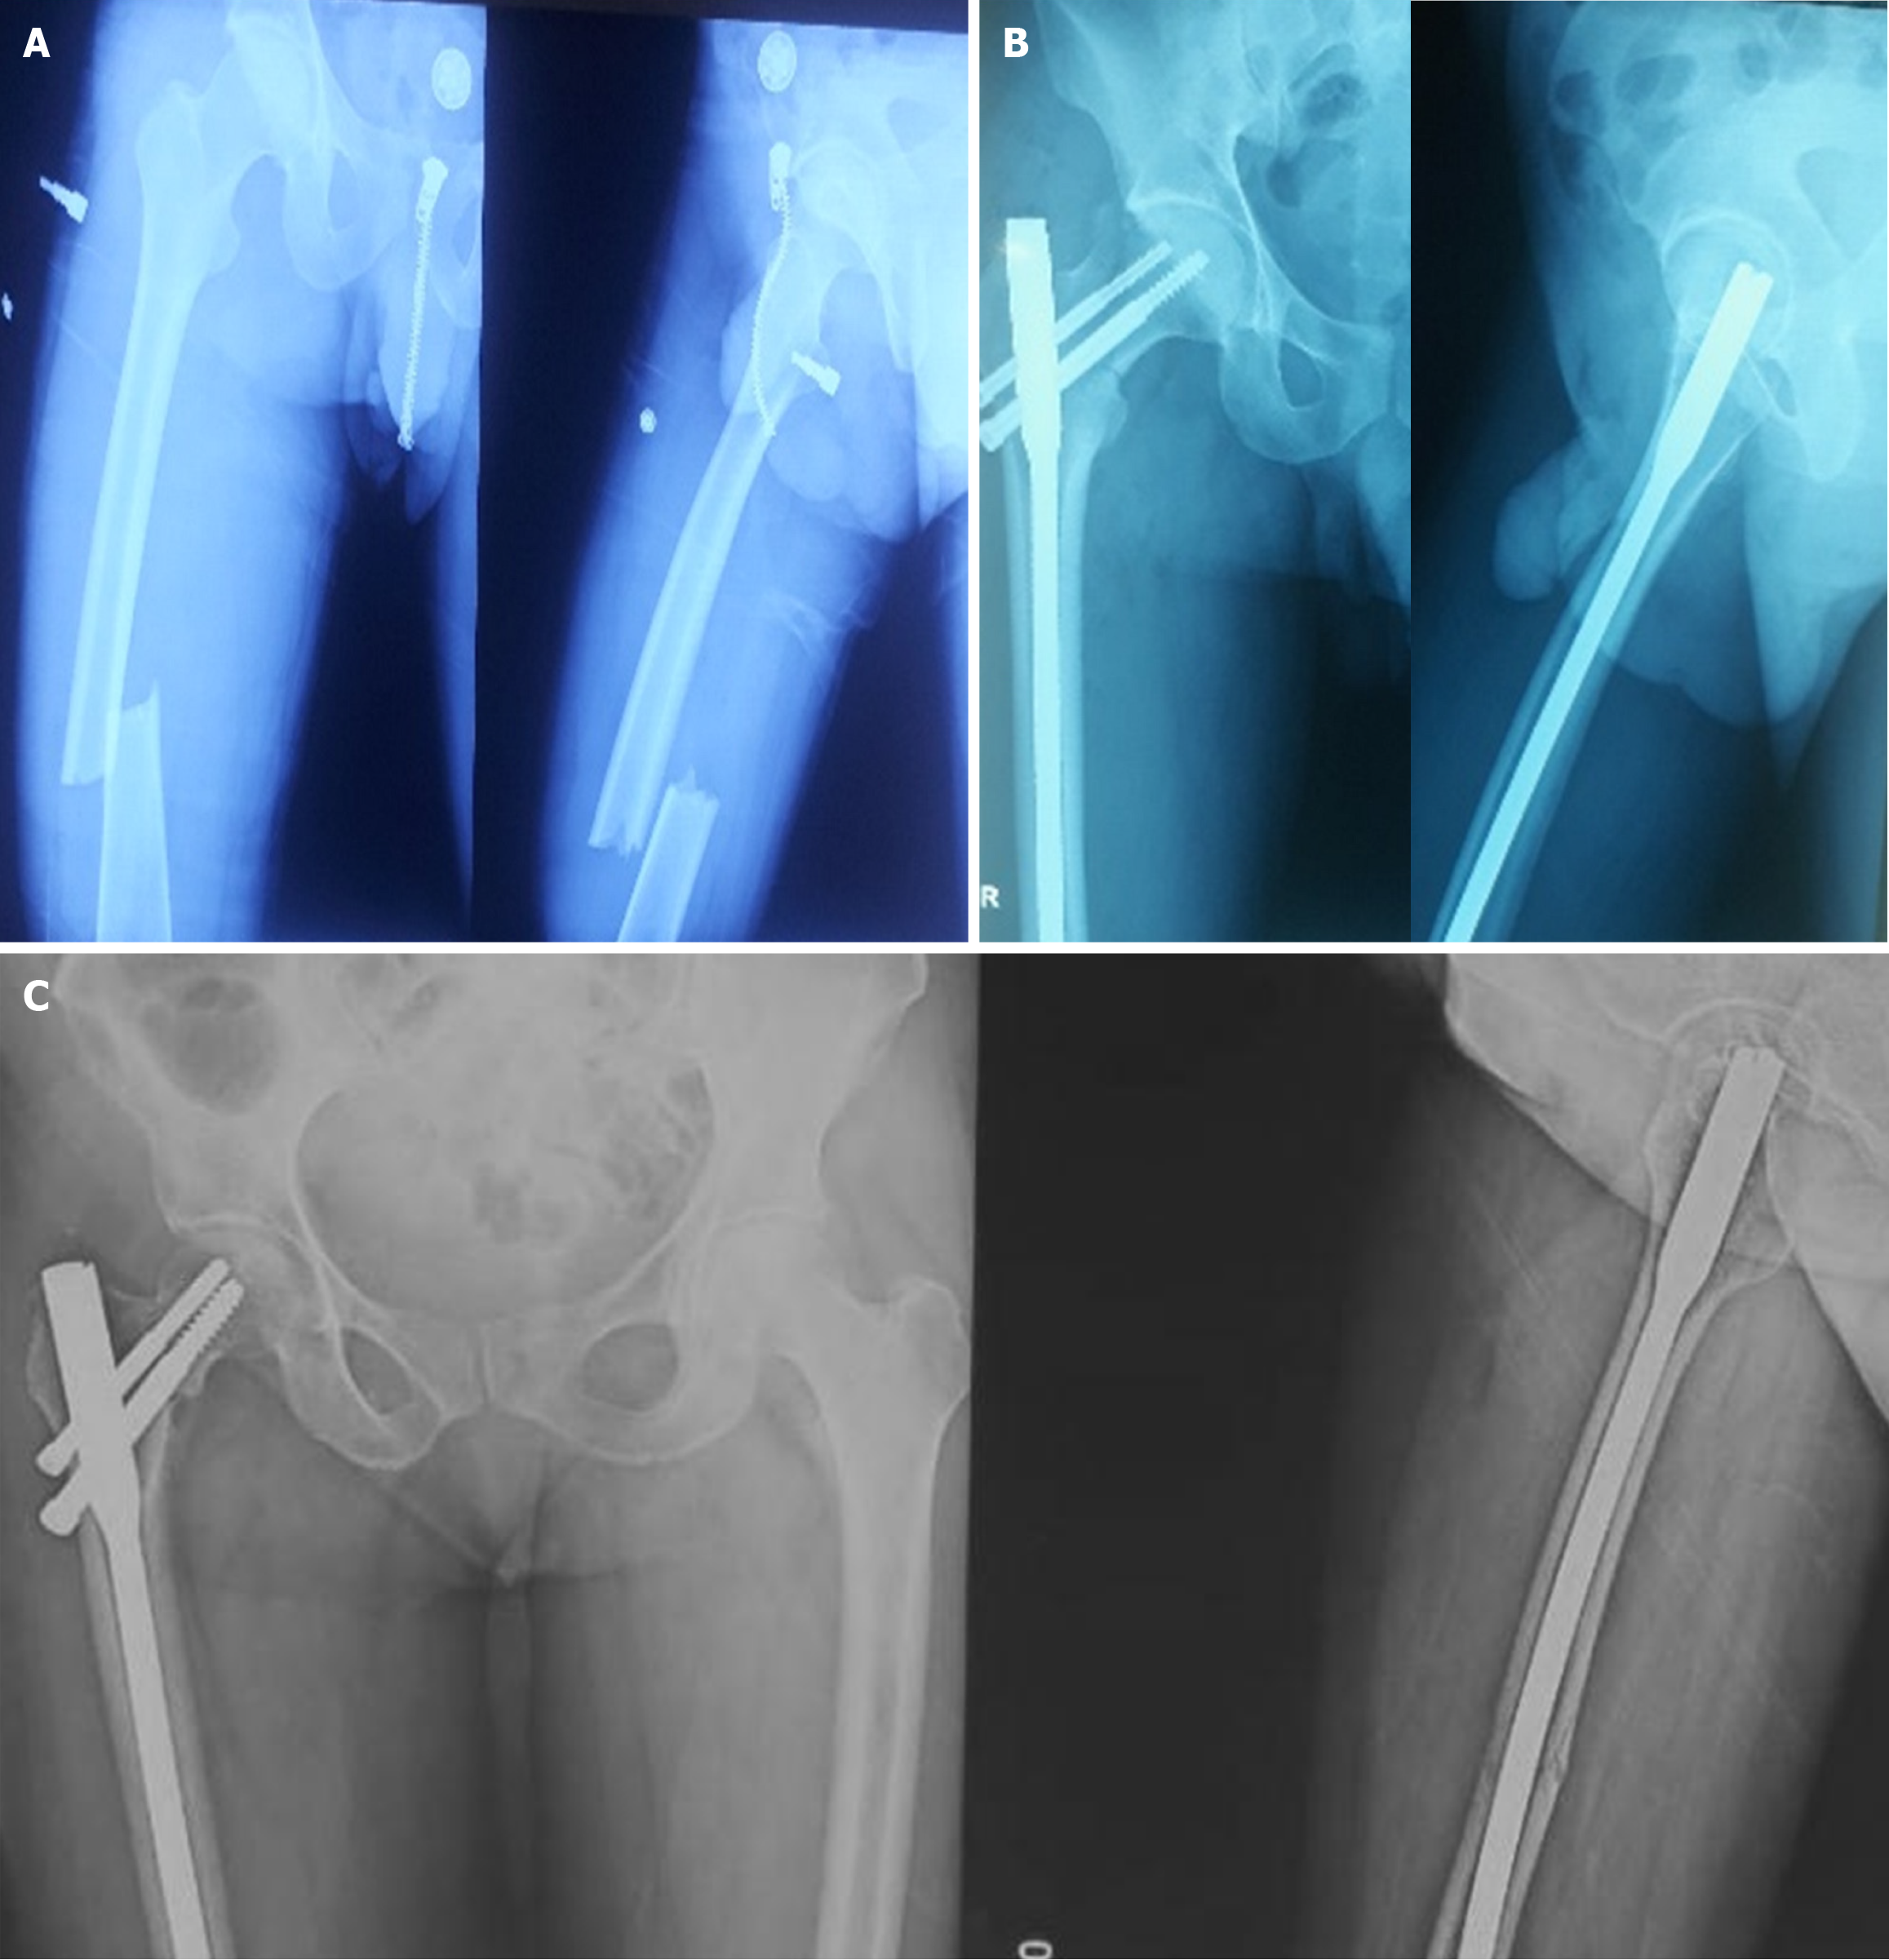

Fractures were diagnosed intraoperatively in 14 cases, immediately postoperatively in 1 case, and during follow-up (within 4 weeks) in 3 cases. The etiological breakdown included erroneous entry point (6 cases) as shown in Figure 3, inadvertent jig hammering (5 cases) as shown in Figure 4, misdirected nail manipulation (3 cases), hoop stress-related fractures (3 cases) as shown in Figure 5, and one case of unexplained origin. Intraoperative fractures were typically identified during final fluoroscopic checks, while postoperative fractures were detected on follow-up radiographs without intervening trauma Figure 6. The list of eitiologies contributing to iatrogenic fractures during femoral nailing is listed in Table 1.

| Hoop stress-related fracture | 3 | Postoperative (≤ 4 weeks) | 1 undisplaced, 2 displaced | CCS (2), hemiarthroplasty (1) |

Among the 18 cases, 11 were undisplaced and 7 were displaced. Fixation methods included long proximal femoral nails (10 cases), cannulated cancellous screws (6 cases) as shown in Figure 6, bipolar hemiarthroplasty (1 case) as shown in Figure 7, and dual implant technique with limited contact dynamic compression plate (1 case) as shown in Figure 7. The “miss-the-nail” technique was employed in cases where the interlock nail remained in situ and removal was deemed risky due to potential displacement as shown in Figure 5 and Table 2.